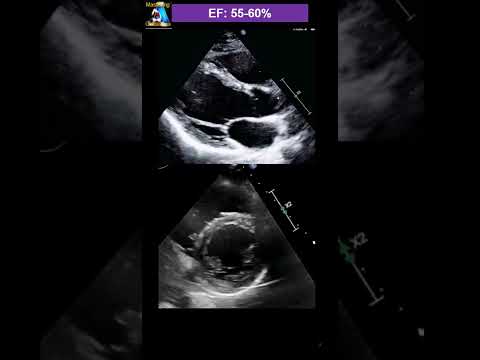

eyeball Guessing Ejection fraction

Visual Guessing Ejection Fraction- Technique & practice

Handy Visual Guessing Ejection Fraction

Ejection Fraction Measurement and Heart Failure

What is the ejection fraction of your heart? What should your EF be?

What does ejection fraction mean for heart failure?

Let’s Talk About Low Ejection Fraction

EP81: Ejection Fraction and Understanding the Percentages